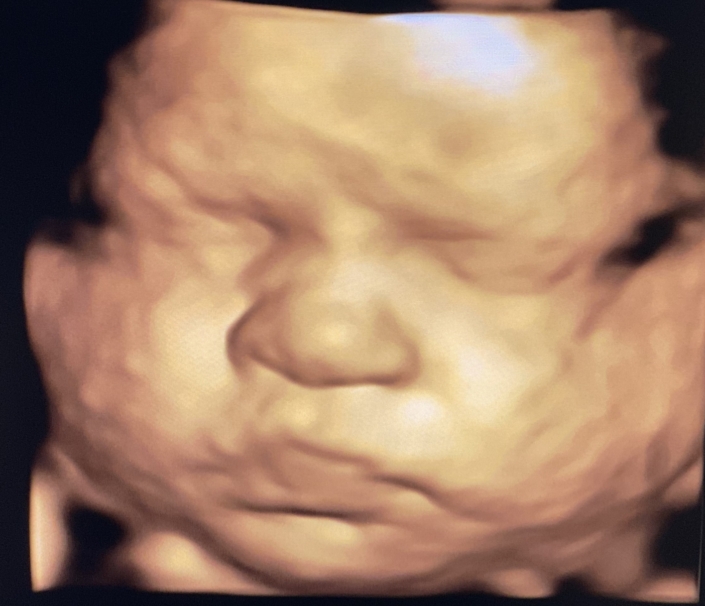

Prenatal Peek®

Prenatal Peek is the leader in 3D 4D Ultrasound. We employ only Certified / Registered Sonographers maintaining unsurpassed standards in 3D ultrasound. You deserve the best! Call us today.